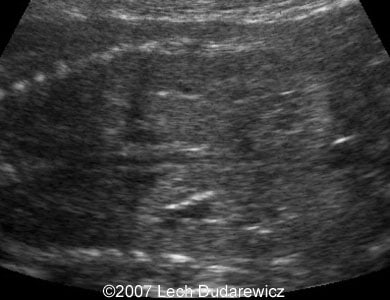

Here are some second trimester ultrasound images of anhydramnios caused by autosomal recessive polycystic kidney disease.

Images 1, 2: Coronal planes through the fetal kidneys with echogenic parenchyma.